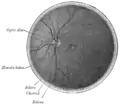

- Interior of posterior half of bulb of left eye. The veins are darker in appearance than the arteries. (Central retinal artery visible but not labeled).

- Horizontal section of the eyeball.

- The terminal portion of the optic nerve and its entrance into the eyeball, in horizontal section.

- Eye vessels